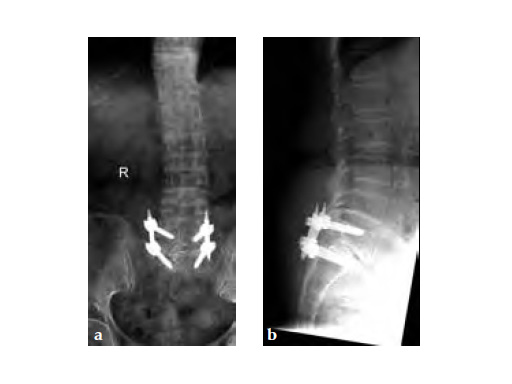

Three weeks prior to her last admission, she complains of recurrent right thigh pain for which epidural analgesics were administered for presumed radiculopathy, however preliminary x-rays and even MRI of the thigh were also taken in view of her primary complaint regarding her right thigh. These investigations did not indicate the possibility of impending bisphosphonate related femur fracture. It is clear from the radiographs that she has an obvious anterolateral bow of her femur and a thickened lateral cortex in the lateral midshaft cortical bone, which may indicate a stress fracture (see Fig 3a-b).

No edema indicated a stress fracture (see Fig 4a-b).

Based on the negative MRI thigh and positive MRI lumbar spine of multiple levels of spinal stenosis, the patient underwent epidural analgesic injection. Patient sustained right femur midshaft periprosthetic fracture the next day after her epidural injection with no trauma.

Notice the fracture decrease the emphasis on the anterolateral bow of the femur (See Fig 5a-b).